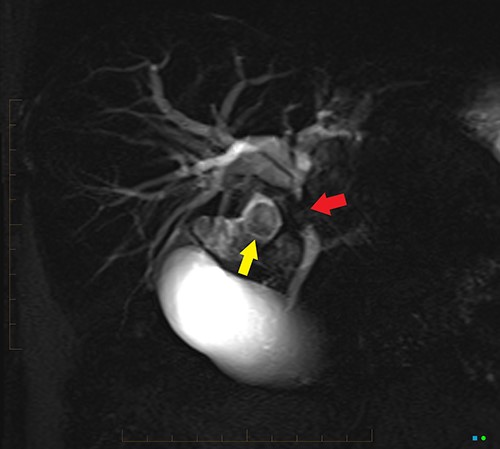

An ultrasound of the abdomen revealed a large gallstone in the gallbladder neck measuring 36 mm with mild biliary dilatation (Fig. 1). Magnetic resonance cholangiopancreatography (MRCP) revealed an irregular long stricture of the extrahepatic bile duct beginning distal to the primary biliary confluence, involving the common hepatic duct for a distance of 20 mm (Fig. 2). A multiphase liver magnetic resonance imaging was performed which confirmed a malignant appearing stricture of the common hepatic duct and showed an ill-defined soft tissue lesion in the porta hepatis between the gallbladder neck and the common hepatic duct (Fig. 3). Her Ca 19.9 was 160 kU/L (ref range < 35 kU/L).

Coronal MPR of late arterial phase CT reveals segmental common hepatic duct stricture with circumferential wall thickening and enhancement (between red arrows) resulting in intrahepatic duct dilatation. Radiopaque calculi (yellow arrows) in the gallbladder.